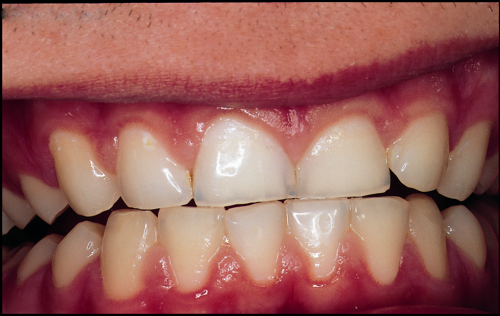

Eksempel på syreskader

Her ses forskellige eksempler på, hvor syre har ætset det meste af emaljen væk. Undersøgelser viser, at hvert 6. barn har syreskader.